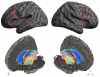

The non-fluent/agrammatic variant of primary progressive aphasia (naPPA) is a young-onset neurodegenerative disorder characterised by poor grammatical comprehension and expression and a disorder of speech sound production. In an era of disease-modifying treatments, the identification of naPPA might be an important step in establishing a specific cause of neurodegenerative disease. However, difficulties in defining the characteristic language deficits and heterogeneity in the anatomical distribution of disease in naPPA have led to controversy. Findings from imaging studies have linked an impairment of this uniquely human language capacity with disruption of large-scale neural networks centred in left inferior frontal and anterior superior temporal regions. Accordingly, the pathological burden of disease in naPPA is anatomically focused in these regions. Most cases of naPPA are associated with the spectrum of pathological changes found in frontotemporal lobar degeneration involving the microtubule-associated protein tau. Knowledge of these unique clinical-pathological associations should advance care for patients with this important class of neurodegenerative diseases while supplementing our knowledge of human cognitive neuroscience.